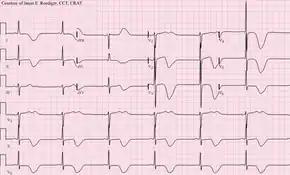

When a stroke has been diagnosed, various other studies may be performed to determine the underlying cause. With the current treatment and diagnosis options available, it is of particular importance to determine whether there is a peripheral source of emboli. Test selection may vary since the cause of stroke varies with age, comorbidity and the clinical presentation. The following are commonly used techniques:

- an electrocardiogram (ECG) and echocardiogram (to identify arrhythmias and resultant clots in the heart which may spread to the brain vessels through the bloodstream);

- a Holter monitor study to identify intermittent abnormal heart rhythms;